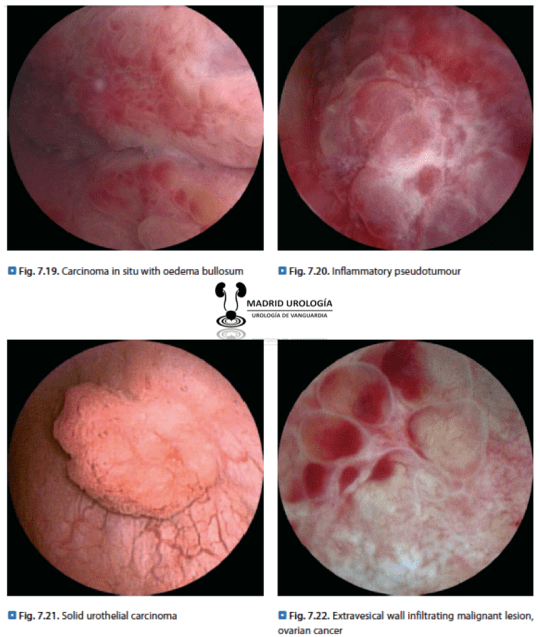

Consiste en la introducción de un Uretrocistoscopio a través del meato uretral y que permitirá la valoración de la uretra y de la vejiga. Aunque la mayoría de lesiones malignas vesicales son bastante bien reconocidas, el urólogo deberá tener alguna experiencia para determinar la presencia de lesiones sospechosas de Cáncer In Situ u otras lesiones menos comunes y benignas (Cistitis folicular, cistitis inespecífica, etc) que puedan ser causa de hematuria.

| En general, las lesiones malignas más frecuentes son fácilmente reconocidas sin embargo existen otras que pueden hacer dudar del diagnóstico. Es importante el estudio de imágenes en cistoscopia. |